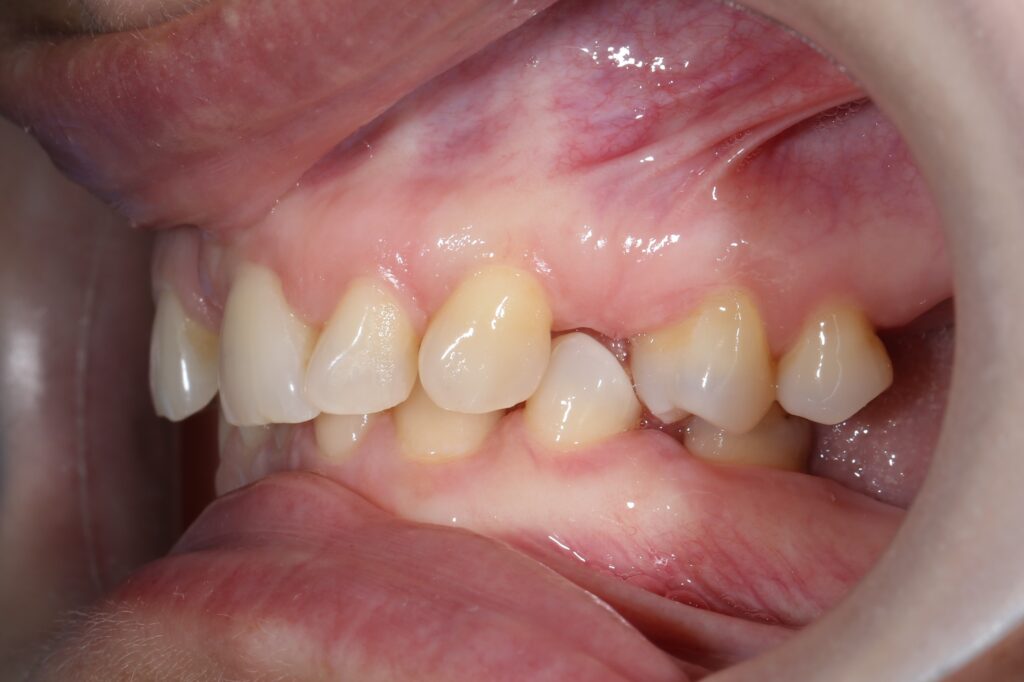

Ситуация до лечения

Пациентка 39 лет была направлена стоматологом-ортопедом для ортодонтической подготовки перед протезированием.

Из-за множественных давних удалений жевательных зубов, произошла деформация зубных рядов, зубы разъехались в область удаленных, что затрудняло протезирование в момент обращения к ортопеду.

Так же можно отметить сильное снижение высоты прикуса (верхние зубы на 100% перекрывали нижние, что вызывало хроническую травму десны), а также повышенную стираемость твердых тканей зубов,

что является следствием повышенной нагрузки, которую много лет испытывали передние зубы, в связи с отсутствием жевательных зубов.

пациент до брекетов